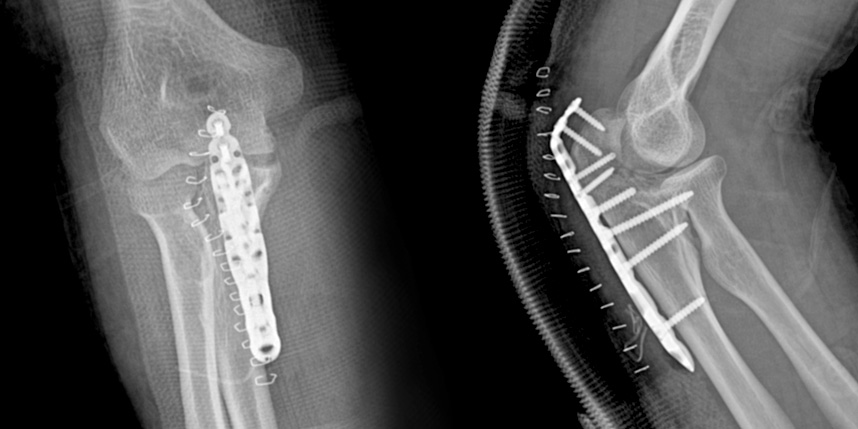

손목 골절

* 환자에게 받은 소중한 자료입니다.